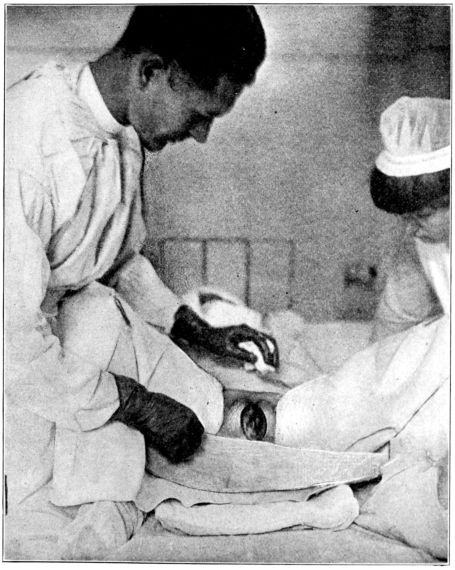

| 103. | Giving chloroform for obstetrical anæsthesia | 287 |

| 104, 105. | Giving ether for obstetrical anæsthesia | 289, 290 |

| 106. | Giving ether for complete anæsthesia | 293 |